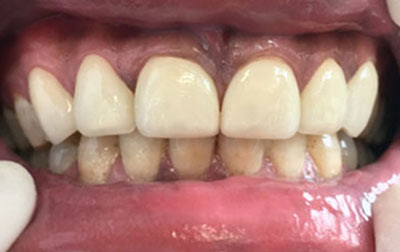

Smile makeover:

Radiating confidence through a beaming smile can truly uplift your spirits. A captivating smile holds significant sway in social and professional spheres, enhancing your overall appeal. However, numerous individuals refrain from revealing their teeth in public or photographs due to personal dissatisfaction. If you find yourself in this category, why not consider allowing us to assist you in attaining the smile you've always envisioned? Embark on a journey toward your ideal smile with our transformative smile makeover. A smile makeover transcends the mere resolution of dental issues as they arise. It constitutes a holistic plan to rejuvenate your smile, intricately tailored to complement your distinct facial features and aesthetic inclinations. The outcomes are nothing short of remarkable—both in terms of your visual transformation and the surge of newfound confidence you'll experience.